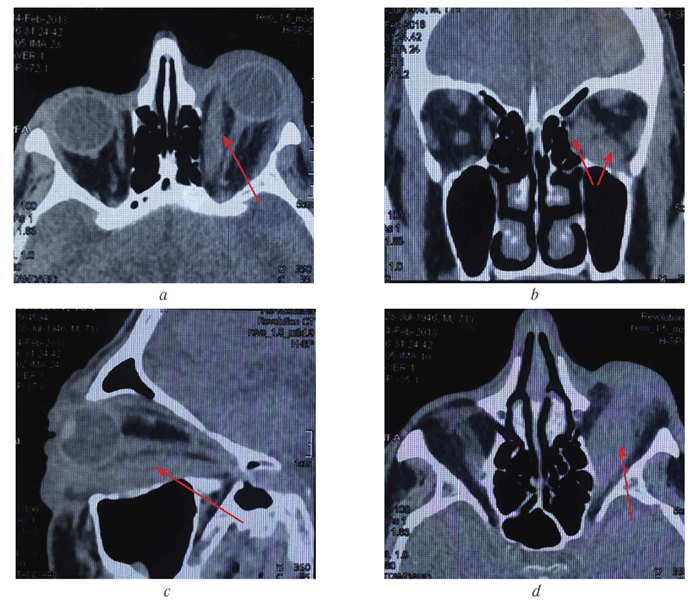

Резко увеличенные нижняя и внутренняя прямые мышцы визуализированы на компьютерных томограммах (рис. 3).

Рис. 3. Компьютерные томограммы орбит того же больного (во всех проекциях визуализируются увеличенные нижняя и внутренняя прямые мышцы (указаны стрелкой); c — визуализируется увеличенная нижняя прямая мышца на всём протяжении от зоны прикрепления к склере до сухожильного кольца

Fig. 3. Computer tomograms of patient’s orbits (in all projections, enlarged lower and inner rectus muscles are visualized (indicated by an arrow); с — an enlarged lower straight muscle is visualized from the attachment zone to the sclera to the tendon ring

Обследован эндокринологом. Диагноз: «Многоузловой зоб, состояние эутиреоза». Длительность спокойного периода, острое начало заболевания на фоне продолжающегося эутиреоза, поражение двух мышц (УЗИ и КТ) послужили основанием для постановки диагноза — первичного идиопатического миозита.